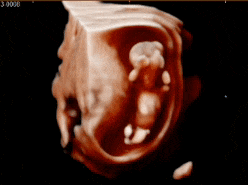

标准NT躺

相信我,这绝对是宝宝一生中最早的一次全身“证件照”,比你拍上半身证件照严格多了。

各种状态的宝贝

趴着的

害羞的

侧躺

倒立

举手

有坐着不爱动的

还有扭来扭去不老实的

甚至能在肚子里练“功夫”

出其不意的一拳,动作快的都看不清ta的招式

悠闲自得

吃着手指还翘着二郎腿

在妈妈的肚子里荡啊荡~